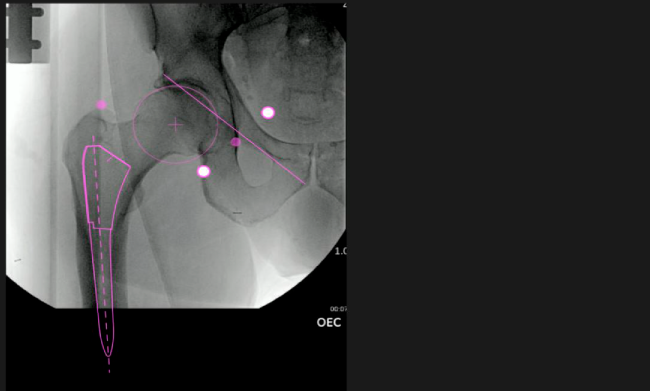

Planeación preoperatoria mediante la creación de plantillas digitales para reemplazo de cadera y análisis intraoperatorio

• Aumenta la precisión y reproducibilidad quirúrgica generando resultados predecibles.

• Datos procesables en tiempo real para la toma de decisiones.

• Mejora los resultados de los pacientes disminuyendo riesgos.

• Favorece la restauración biomecánica del offset femoral.

Beneficios de la planeación preoperatoria con Velys Hip Navigation ™

• Disponibilidad de plantillas digitales de cadera.

• Expediente histórico y personalizado, optimiza la planeación con el calendario de casos realizados en Velys TM y utiliza los íconos interactivos para una rápida revisión.

• Espacio colaborativo: puede compartir los casos entre cirujanos y sus equipos mediante la funcionalidad de intercambio de información.

Mayor nivel de información intraoperatoria facilita la colocación correcta de los implantes:

• Inclinación y anteversión de la copa acetabular para una correcta colocación del implante.

• Desplazamiento y offset para posicionamiento óptimo del componente (vástago) femoral.

• Verificación de la posición deseada del implante que potencialmente puede ayudar a reducir la probabilidad de dislocación protésica y aumentar la estabilidad de la articulación.

• Anotaciones digitales y herramientas de análisis de longitud de pierna.

• Con tecnología ONETRIAL® que calcula automáticamente el cambio en la longitud de la pierna y el desplazamiento para todas las combinaciones de implantes en una tabla fácil de leer.